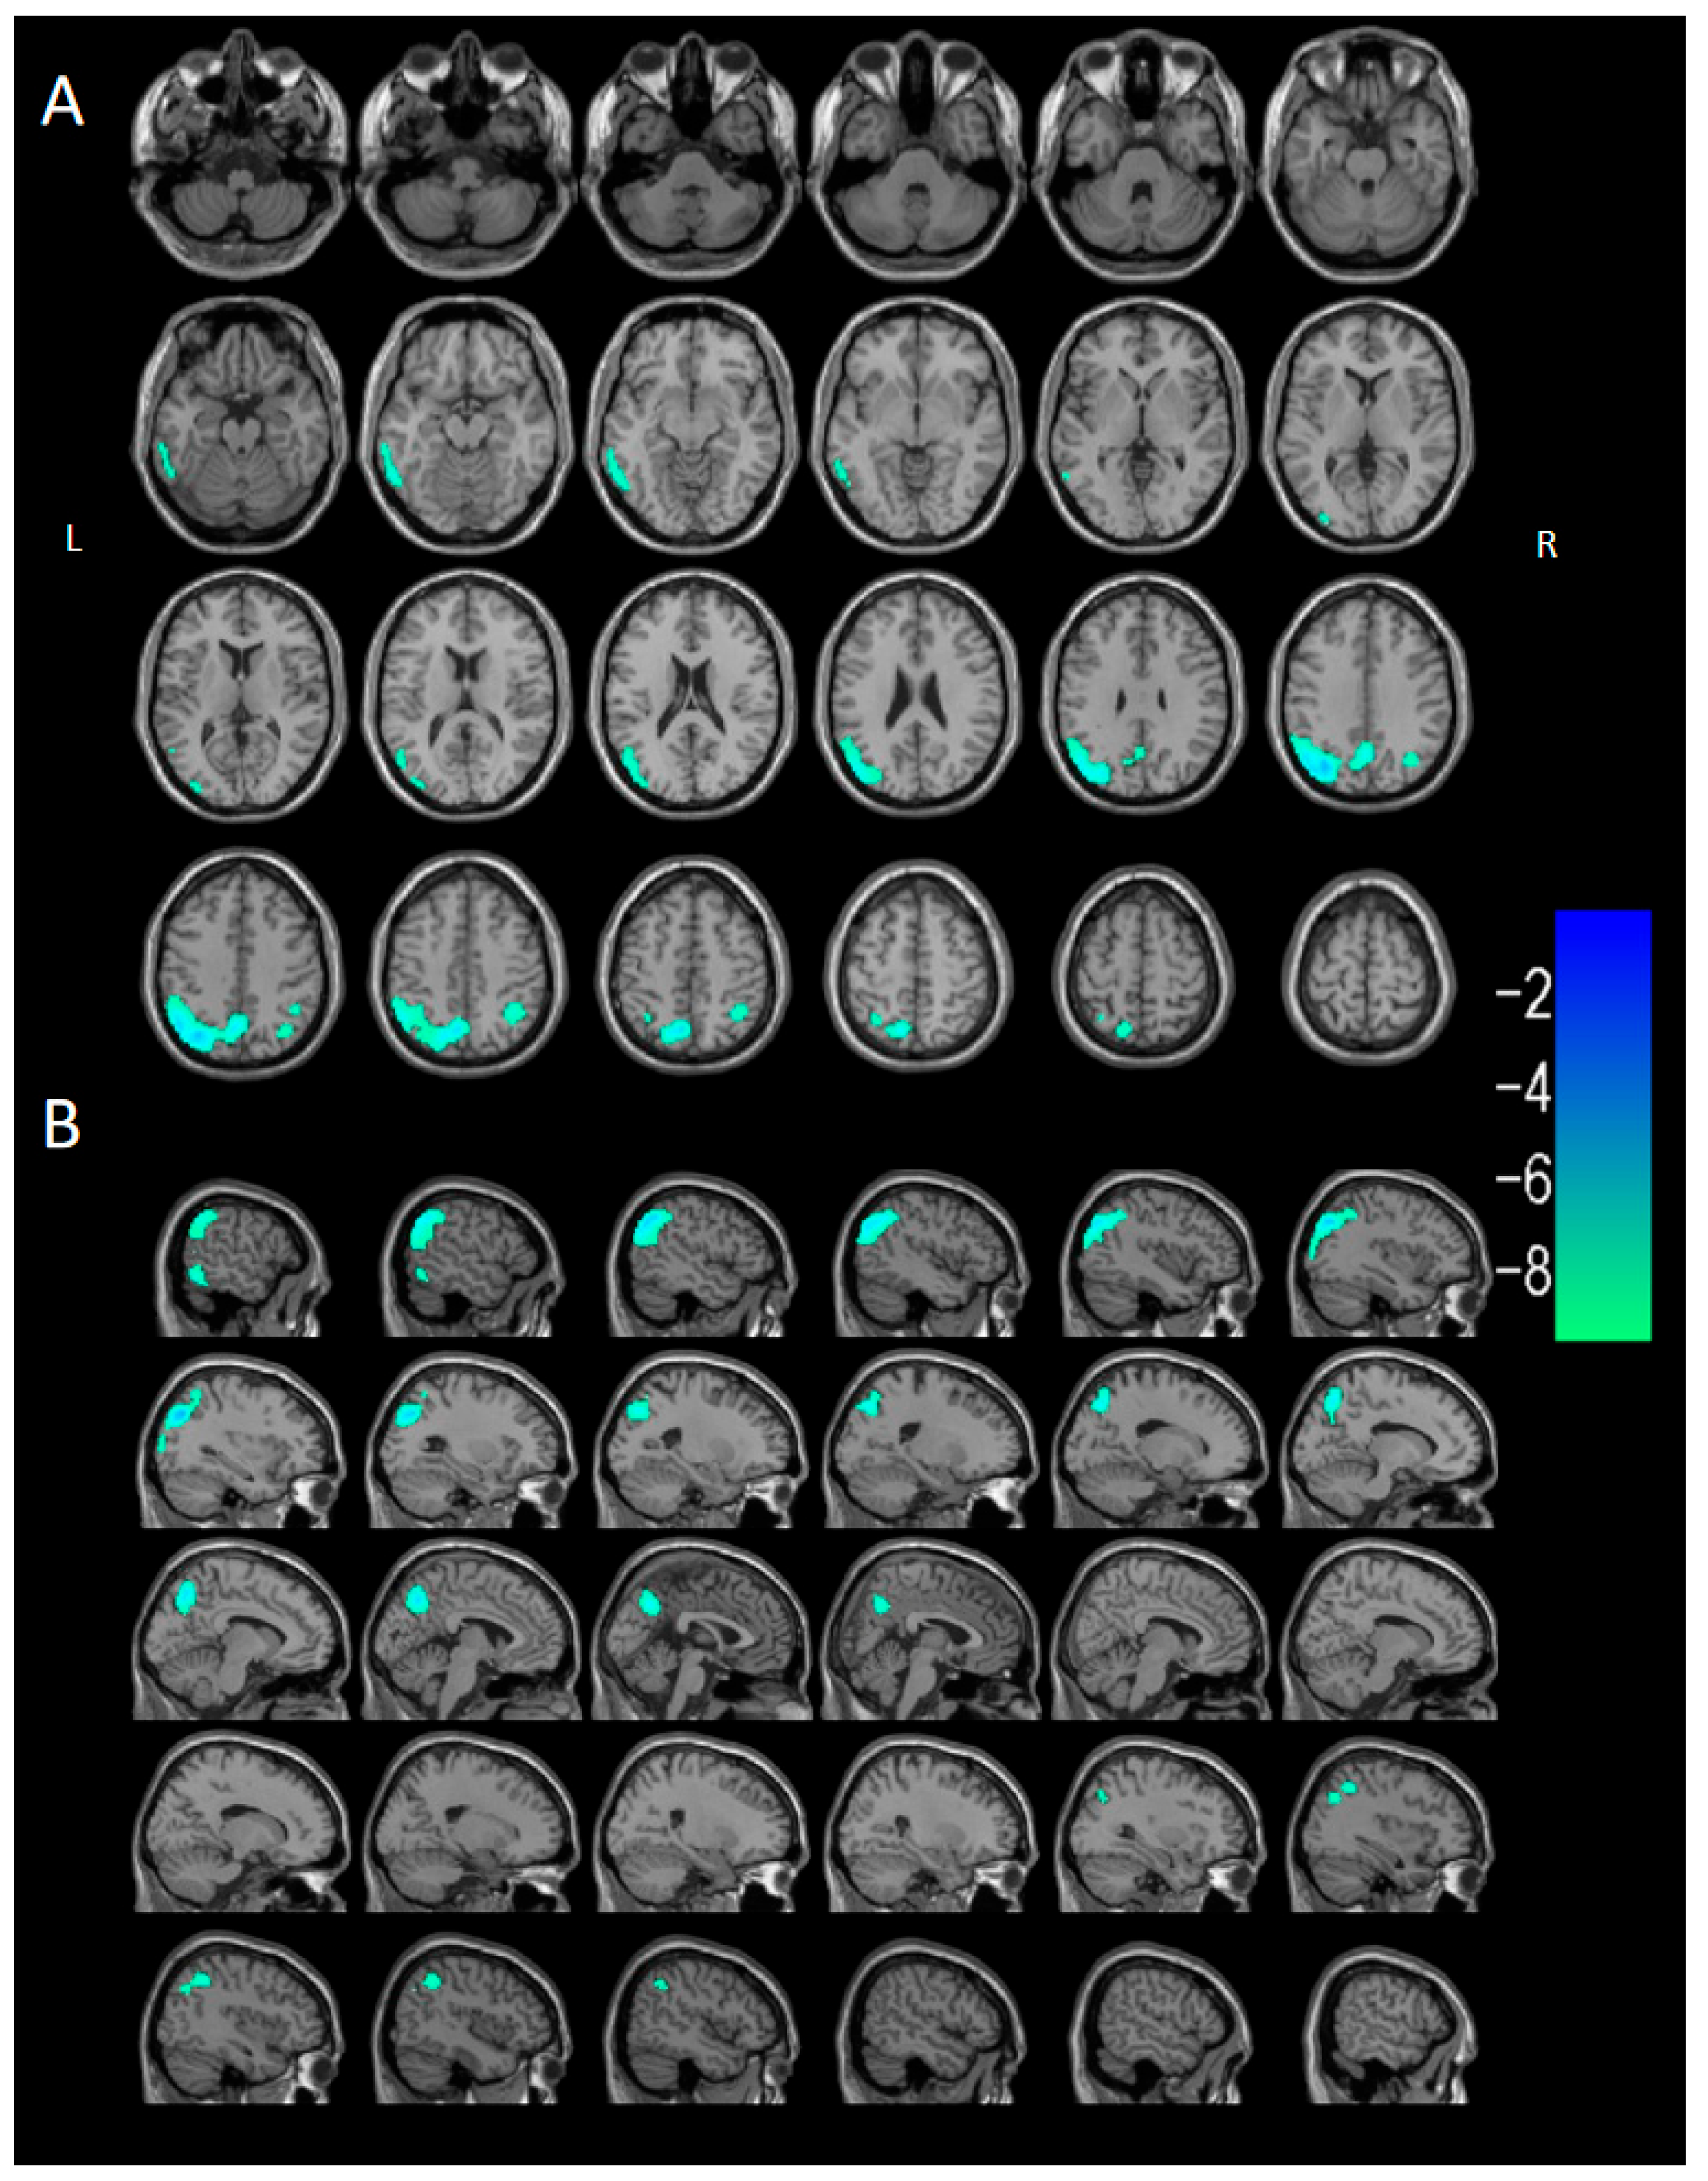

3.2.3. Voxel-Based Semi-Quantitative Analysis

| Brain Region of Cluster | Cluster Size (Voxels) | Peak t | Peak MNI Coordinates | ||

| DLB < HC | |||||

| Cluster 1 | 29,280 | −11.5121 | −44 | −74 | 36 |

| Occipital_Mid_L (aal) | 2736 | ||||

| Temporal_Mid_L (aal) | 2409 | ||||

| Parietal_Inf_L (aal) | 1864 | ||||

| Temporal_Mid_R (aal) | 1836 | ||||

| Precuneus_L (aal) | 1653 | ||||

| Precuneus_R (aal) | 1609 | ||||

| Temporal_Inf_L (aal) | 1536 | ||||

| Occipital_Mid_R (aal) | 1460 | ||||

| Angular_R (aal) | 1460 | ||||

| Temporal_Inf_R (aal) | 1337 | ||||

| Parietal_Sup_L (aal) | 1167 | ||||

| Angular_L (aal) | 1104 | ||||

| Parietal_Inf_R (aal) | 1056 | ||||

| SupraMarginal_R (aal) | 847 | ||||

| Parietal_Sup_R (aal) | 814 | ||||

| Occipital_Inf_L (aal) | 701 | ||||

| Occipital_Sup_L (aal) | 669 | ||||

| SupraMarginal_L (aal) | 656 | ||||

| Occipital_Sup_R (aal) | 491 | ||||

| Fusiform_L (aal) | 479 | ||||

| Cuneus_L (aal) | 402 | ||||

| Cuneus_R (aal) | 279 | ||||

| Occipital_Inf_R (aal) | 234 | ||||

| Temporal_Sup_R (aal) | 216 | ||||

| Calcarine_R (aal) | 194 | ||||

| Lingual_R (aal) | 185 | ||||

| Lingual_L (aal) | 147 | ||||

| Calcarine_L (aal) | 136 | ||||

| Temporal_Sup_L (aal) | 128 | ||||

| Cingulum_Post_L (aal) | 70 | ||||

| Cingulum_Post_R (aal) | 33 | ||||

| Cluster 2 | 1037 | −6.4095 | 42 | 32 | 38 |

| Frontal_Mid_R (aal) | 908 | ||||

| Frontal_Inf_Tri_R (aal) | 57 | ||||

| Cluster 3 | 2379 | −6.5266 | −32 | 24 | 52 |

| Frontal_Mid_L (aal) | 1628 | ||||

| Frontal_Inf_Tri_L (aal) | 473 | ||||

| Frontal_Sup_L (aal) | 104 | ||||